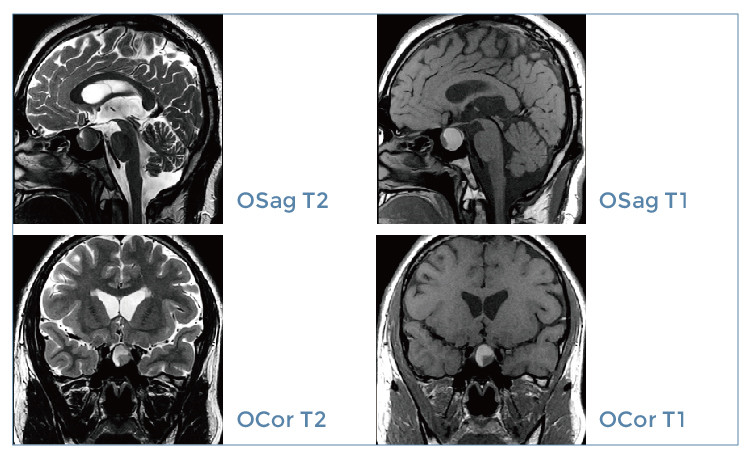

【朗润影像档案】20200104磁共振影像病例结果讨论

【朗润影像档案】磁共振影像病例分享(编号20200104)